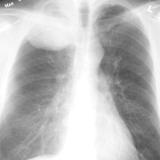

Lung Cancer

Nodules & Masses

Album: Nodules & Masses